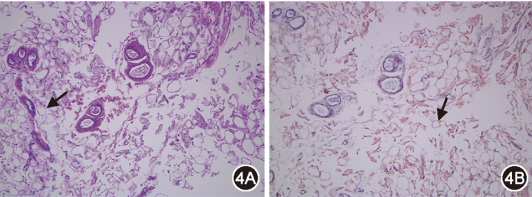

图5  治疗后(2025年10月23日)胸部CT:双肺间质病变、胸腔积液较治疗前轻度加重

后续患者于血液科治疗,目前已完成8程Dara-VenD治疗:达雷妥尤单抗1 800 mg/次、1次/周;维奈克拉200 mg/次(因白细胞低减量)、1次/d;地塞米松20 mg/次、1次/周。气短好转,右乳及下肢水肿部分减轻,可耐受家务活动,监测指氧饱和度94%左右。治疗9个月后复查血游离轻链κ下降至9.9 mg/L,血液学完全缓解,心脏病情稳定,CT示双肺间质病变、胸腔积液轻度加重(图5),考虑和已沉积的淀粉样物质清除困难有关,但病情进展速度减缓。

患者根据血液科医师制定的方案进行全身治疗,尽管已达血液学缓解,其肺部与胸膜病变却持续进展。肺间质淀粉样变出现影像学改善极为少见,可能与已沉积的淀粉样物质难以自行清除,并持续导致器官损伤有关[14, 15]。然而,目前暂无药物获批于清除沉积物,治疗仍以抗浆细胞及支持治疗为主。CAEL-101为靶向淀粉原纤维单抗,可清除器官中的纤维聚集体,已在Ⅰ/Ⅱ期试验中验证疗效,有望为改善预后带来突破[15]。